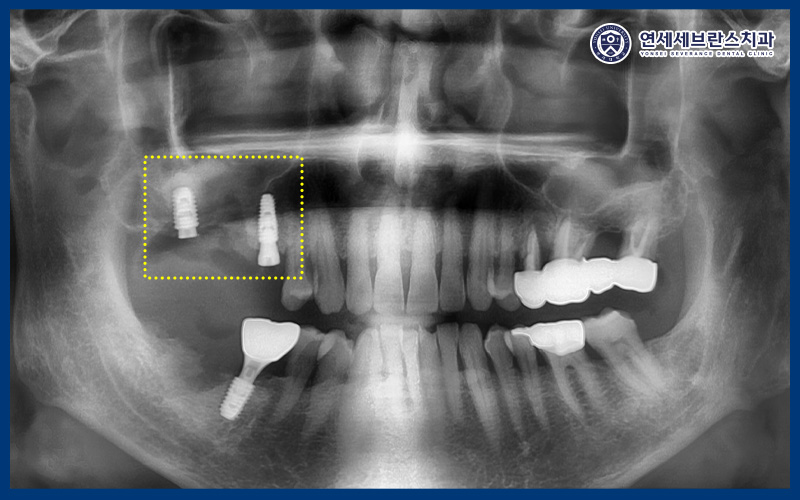

CT로 비교해 보았을 때,

상악동거상술을 통해

부족했던 상악동 하방 공간을 확보하여

임플란트 식립이 가능한 환경을

조성한 것을 확인할 수 있었습니다.

25.06.18 / 25.09.18

그리고 오른쪽 아래는

발치 후 뼈이식만 먼저 진행하여

충분한 치유와 안정화를 도모하였습니다.

이후 이식한 뼈가 잘 결합되어

임플란트 식립을 진행하였습니다.